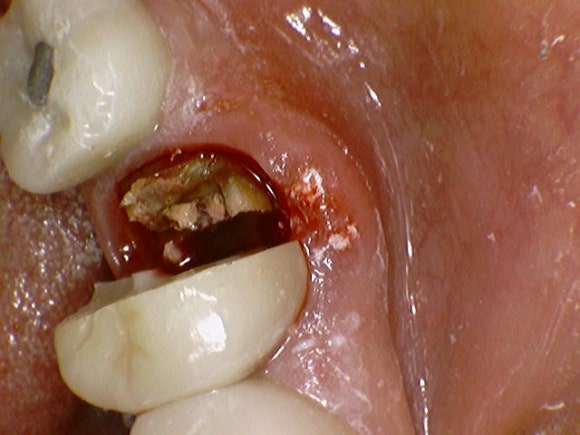

20240809

크라운을 뜯으니 썩은 뿌리가 보입니다.

뿌리가 썩으면 치아는 더 이상 기능을 할 수가 없습니다.